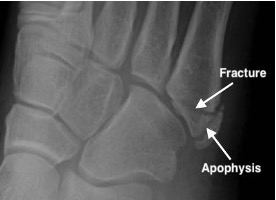

Fifth metatarsal base fractures

Avulsion fracture

- Caused by pull off peroneus brevis tendon

- Differentiate from normal unfused apophysis:

- the apophysis lies parallel to the long axis of the MT

- a fracture line lies transverse to the long axis of the MT

Avulsion fracture base 5th metatarsal and normal apophysis